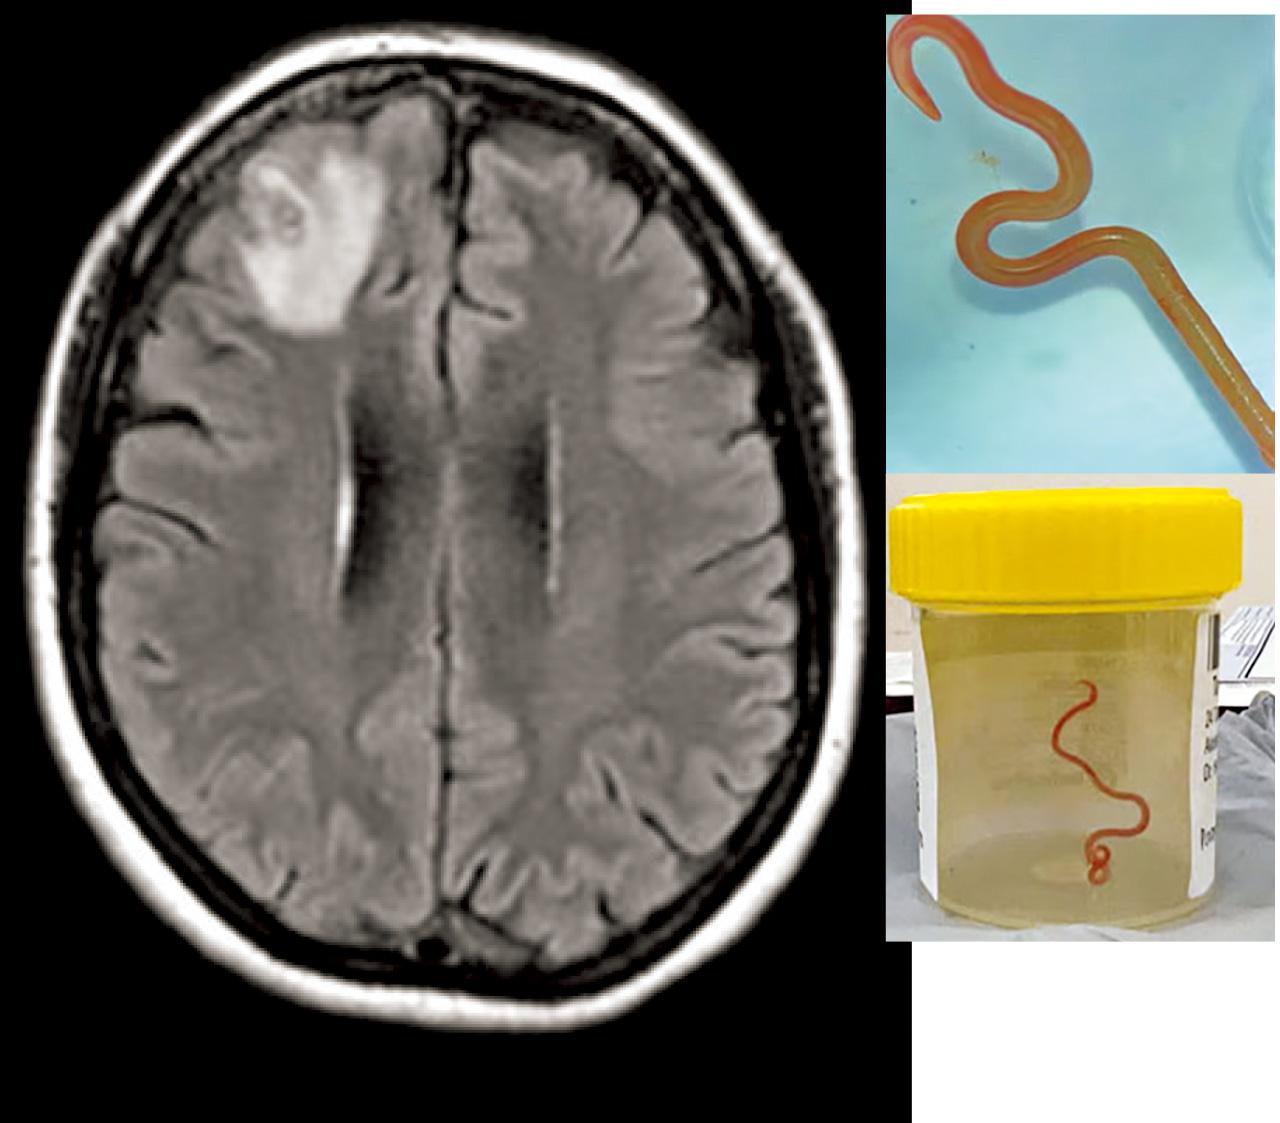

(上圖)醫生發現該婦人腦部異常,開腦取出8厘米蛔蟲。(下圖)從婦人腦部取出的蛔蟲。(互聯網)

該名婦人因持續3周出現腹痛、腹瀉、乾咳、發燒與盜汗情況,2021年1月到醫院求醫;及至去年再出現健忘及抑鬱症狀,被轉診至坎培拉醫院。該院神經外科醫生班迪(Hari Priya Bandi)看過她的磁力共振掃描(MRI)後,認為其大腦有異常,必須進行手術,結果醫生從婦人腦部裡取出一條寄生蟲。